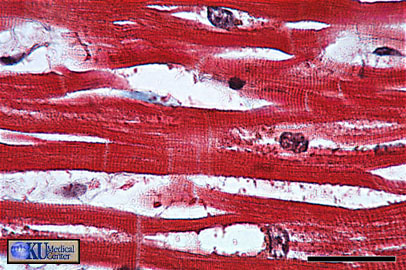

Cardiac Muscle: Longitudinal cardiac muscle can be identified by centrally placed round to oblong nuclei, striations, branching, and intercalated discs (arrow).